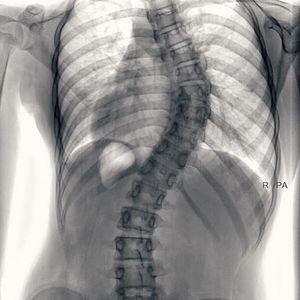

What is your diagnosis?